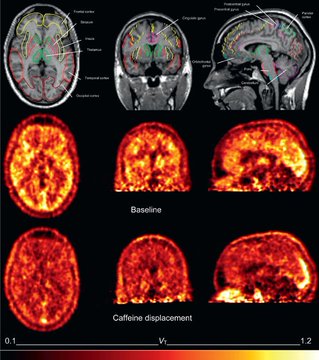

Au cours des 10 dernières années, j'ai bu 3 à 5 tasses de café par jour.